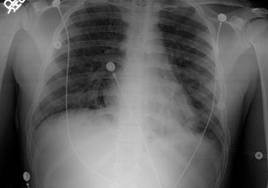

Фиброзно-кавернозный туберкулез

Такая форма туберкулеза является хронической запущенной стадией, которая очень сложно поддается любым методам лечения. Характеризуется она появлением фиброзных каверн, быстрым развитием фиброзных изменений.

Эта форма сама опасная при возникновении эпидемий, так как в фиброзных полостях скапливаются микобактерии туберкулеза, то есть заболевший является бактериовыделителем. Читать далее